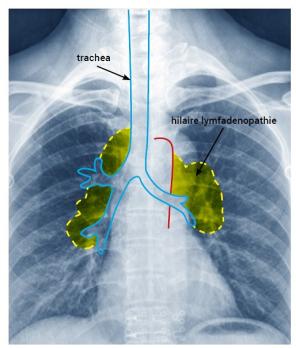

Trombose bij COVID-19-infectie Lees meer over Trombose bij COVID-19-infectie Trombose bij COVID-19-infectie

In december 2019 ontstond in Wuhan (China) een nieuw virus genaamd SARS-CoV-2, dat COVID-19 (coronavirus disease 2019) kan veroorzaken. Het virus karakteriseert zich door het veroorzaken van een bovensteluchtweginfectie, die zich snel ontwikkelt tot een longontsteking (pneumonie) en uiteindelijk kan leiden tot respiratoir falen. Het virus heeft zich snel verspreid en op 11 mei 2020 verklaarde de World Health Organisation (WHO) dat het virus een pandemie heeft veroorzaakt.